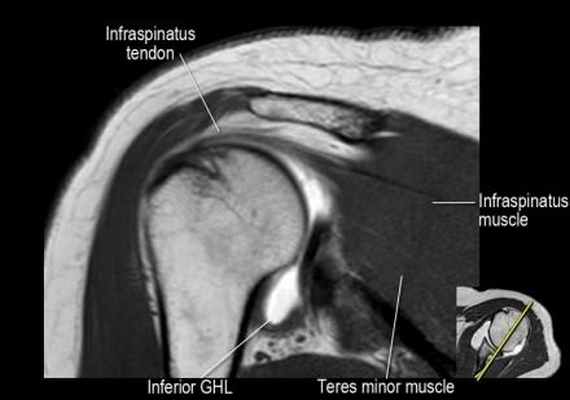

Изображение задних отделов плечевого сустава.

Отображены надостная, подостная и малая круглая мышцы и их сухожилия. Все они прикрепляются к большому бугорку плечевой кости. Сухожилия и мышцы манжеты вращателей участвуют в стабилизации плечевого сустава во время движения. Без манжеты вращателей головка плечевой кости частично сместилась бы из суставной впадины, уменьшив силу отведения дельтовидной мышцы (мышцы вращательной манжеты координирует усилия дельтовидной мышцы). Повреждение манжеты вращателей может привести к смещению головки плечевой кости кверху, в результате вызвая высокое стояние головки плечевой кости.